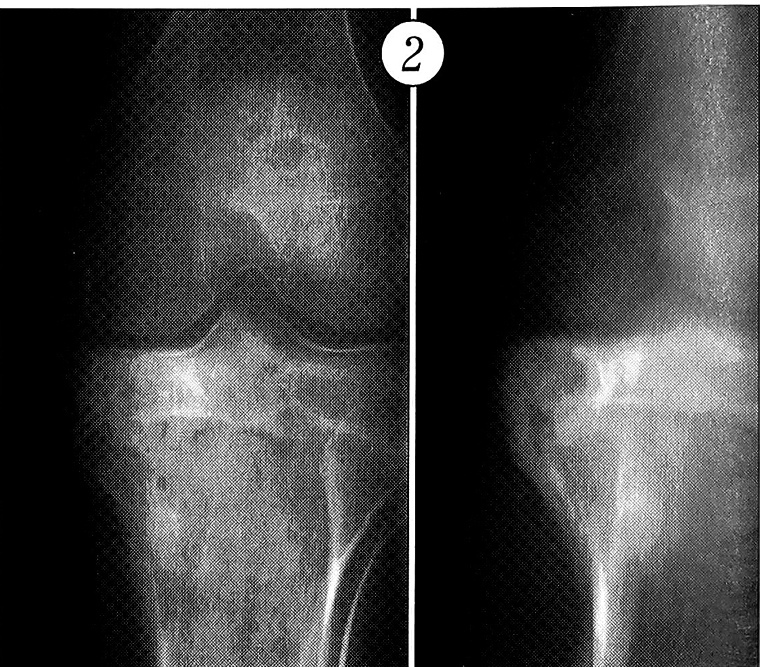

При «типичной» форме хондробластомы рентгенологическая картина характеризуется наличием эксцентрически расположенного остеолитического очага деструкции диаметром от 1,5 до 5 см, округлой или овальной формы, с четким контуром. От смежных отделов кости очаг отграничен полоской склероза. В половине наблюдений отмечались характерные крапчатые включения. В ряде случаев включения имели вид хлопьев ваты. Эксцентрическое расположение очага деструкции и рост опухоли приводили к истончению и «вздутию» коркового слоя. Разрушение коркового слоя с образованием экстраоссального компонента опухоли выявлено у 8 больных. Нередко определялись частично слившиеся периостальные наслоения, располагавшиеся на некотором удалении от очага, в метадиафизарном отделе (табл. 4, рис. 2).

Рис. 2. Больной X. 16 лет. Хондробластома проксимального метаэпифиза левой большеберцовой кости. Рентгенограммы в прямой и боковой проекции: разрушение ростковой пластинки; округлый очаг деструкции с крапчатыми включениями известковой плотности; частично слившиеся периостальные наслоения в отдалении от очага.